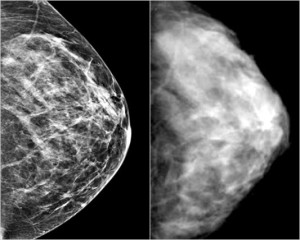

Screening al seno: riduce il rischio di morte per cancro

Lo screening riduce significativamente le morti per cancro al seno, secondo un nuovo studio norvegese pubblicato sul ‘British Medical Journal’.